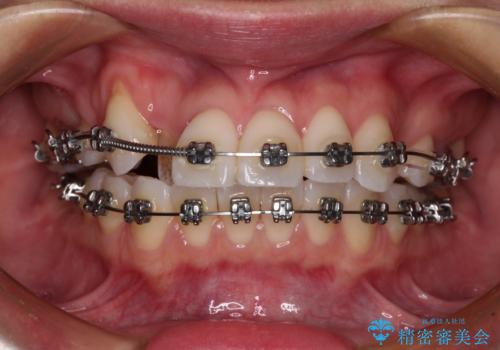

- 八重歯と、それによる正中のズレを気にして来院された患者様です。

口元の突出感は気にしていなかったため、上顎の左右第一小臼歯を抜歯することで、八重歯の解消と上顎の正中を改善していくこととしました。

奥歯の咬み合わせを維持しながら正中位置を改善するために、補助装置を使用しました。

予定より期間がかかりましたが、上下の正中位置を綺麗に一致させることができました。